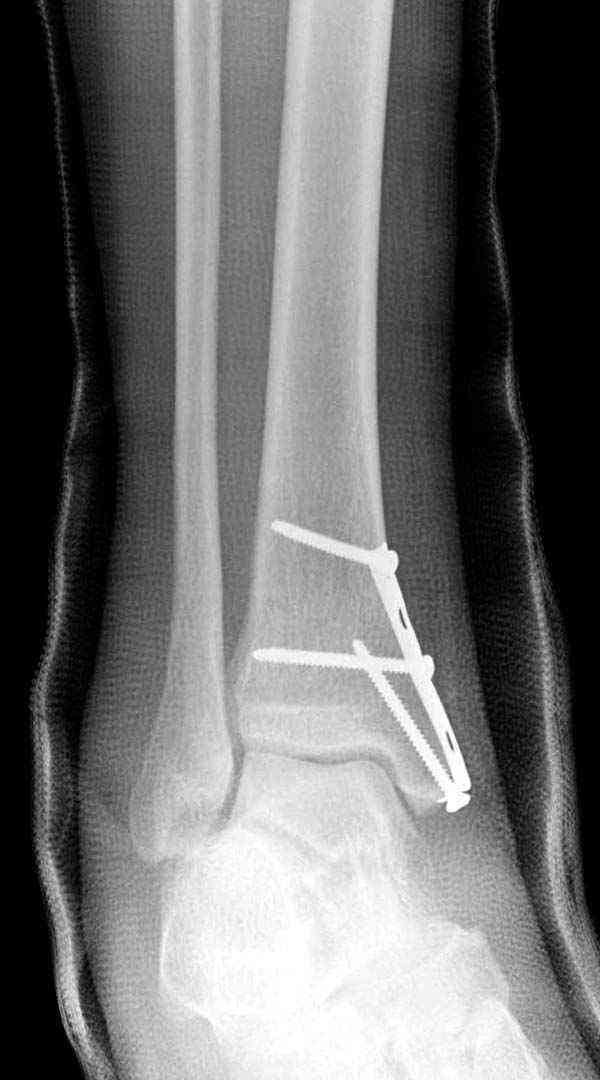

Нет первичных снимков, перелом очень низкий и под большим сомнением диагноз разрыва синдесмоза. Медиальная сторона отрепонирована на "хорошо" и, по-видимому, прорезание проволоки произошло во время операции. Без снимков трудно судить о высоте малоберцовой, а лодыжка находится в варусе. Лагирование получилось, но возле тонких шурупов передне-задний шуруп выглядит немного тяжеловато.

Во всех руководствах АО имеется описание техники применения низкопрофильных пластин 1/3 трубки, которые могут быть применены для фиксации наружной лодыжки. Фиксацию проводят кортикальными 3.5 мм шурупами, и если дистальная фиксация недостаточная, тогда усиливают конструкцию созданием hook plate. Сгибая конец пластины на последнем отверстии, внедряют его в дистальный отдел, и тем самым создается дополнительная фиксация.

Современные преконтурированные пластины не имеют таких недостатков, и разделяются на правые и левые, а также на латеральные и задние. Множественные дистальные шурупы 2.7 мм уменьшают подкожное раздражение, и такой имплант можно оставить на долгий срок без удаления.

Медиальная лодыжка фиксируется каннюлированными лодыжечными шурупами перкутанно, а неточная репозиция (интерпозиция) является показанием к открытой технике. При больших вертикальных фрагментах нужны противоскользящие медиальные пластины.

Здесь несколько частных случаев: перелом голеностопа со сравнительными снимками и разрыв синдесмоза, а также медиальная Hook пластина.